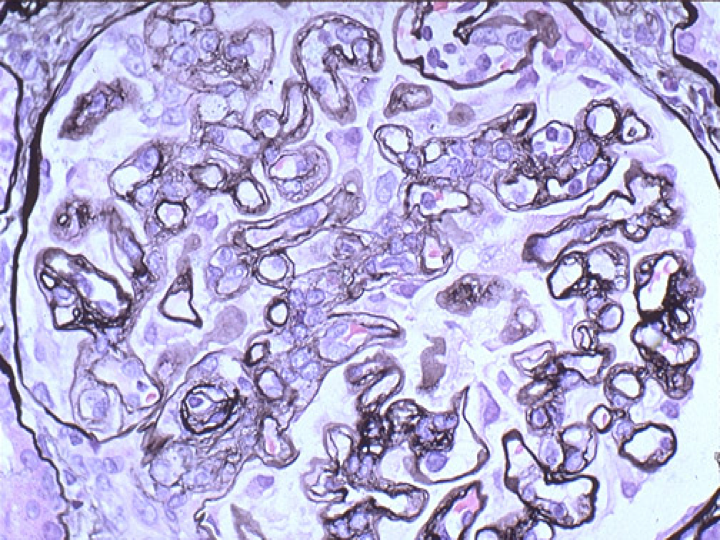

光镜下,Ⅰ型典型的病变是,弥漫性系膜细胞和系膜基质重度增生,沿内皮细胞和基底膜之间长入或插入(mesangial interposition),使毛细血管壁增厚,镀银染色或PAS染色基底膜呈双层(double contour)或多层状改变,这是由于系膜基质插入造成的。由于系膜细胞和系膜基质重度增生,系膜区域扩大导致肾小球呈明显的分叶状。Ⅱ型膜增生性肾小球肾炎也呈现这些病变,但与Ⅰ型相比,系膜增生轻,肾小球分叶状结构不明显。

(镀银染色或PAS染色基底膜呈双层(double contour)或多层状改变,这是由于系膜基质插入造成的)